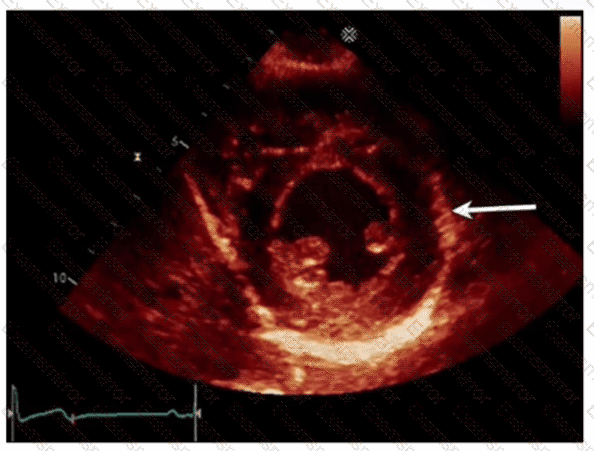

Which echogenic structure is indicated by the arrow on this image?

Which left ventricular regional wall segment is indicated by the arrow on this image?